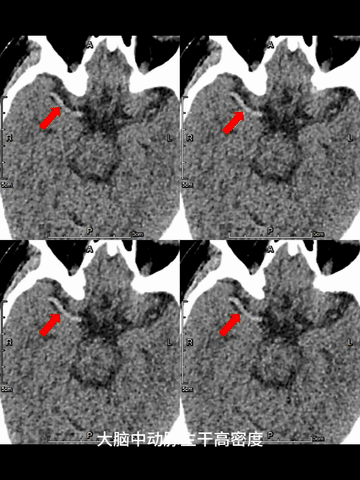

2、急诊CT平扫薄层重建和颅脑4D_CTA结果提示:右ICA远端至M2近端长段高负荷血栓。

CT平扫:ASPECT是9分,薄层MIP重建于右ICA末端至M2近端见长段血栓高密度影。